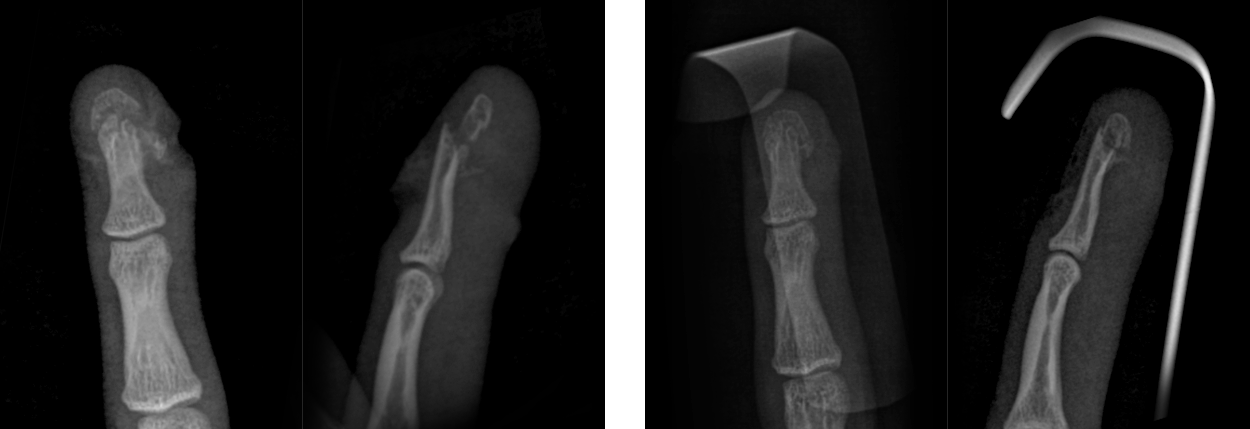

봉합술 후 핀 고정 없이도 골절편이 맞춰진 모습